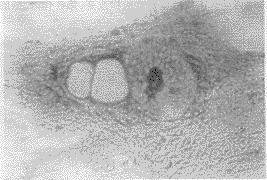

2.1 原代和传代培养 将4种不同来源3种不同种属的晶状体囊膜片置入培养瓶中培养,观察发现新生小牛、兔和胎儿的囊膜片在24~48h就有上皮细胞自囊膜片生长移出,而成人囊膜片在40~72h才可见有细胞自囊膜片生长移出,外观呈芽胞状(见图1),近囊膜片处细胞生长密集,呈多角形。远离囊膜片处细胞生长稀疏,胞体延伸,培养的小牛、兔晶状体上皮细胞约需6~10d细胞发生融合长满瓶底,胎儿约需9~12d,成人约需11~14d;经消化后按1∶2传代的小牛、兔晶状体上皮细胞生长迅速,约3~4d细胞可达融合,融合后的细胞呈多角形、椭圆形,大小基本一致;胎儿晶状体上皮细胞生长稍有所缓慢,约6~8d细胞发生融合,经Gimsa染色见细胞呈上皮细胞样外观,胞体边界清,胞浆呈均匀的粉红色,以及呈紫红色的单或双核(图2);而不同年龄的人晶状体上皮细胞生长更加缓慢,但形态一致,约需7~14d细胞才达到融合;传代至第3代,小牛、兔晶状体上皮细胞虽生长迅速,但部分细胞形态已呈现出梭形的成纤维细胞的外观(图3),至第5代大部分细胞形态都发生了如此改变,胞内可见网状结构,第6~7代时,细胞生长缓慢,胞内网状结构增多,出现空泡样改变(图4)。第8代时,生长特别缓慢,胞内网状结构及空泡样改变明显增多;而胎儿和不同年龄人晶状体上皮细胞传代至第4代才可见细胞梭形样改变,在第6~7代时胞内也可见有网状结构及空泡样改变,第8代时,细胞也发生衰老。

Figure 2 The configuration of cultured primary fetus lens epithelial cells displayed,×200LM 原代培养的胎儿晶状体上皮细胞形态,×200LM